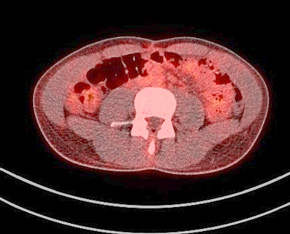

Figure 9. A normal finding of post-transplant PET/CT Scan

One year after the operation, a PET/ CT scan performed showed normal distribution of F-18 FDG and no signs of residual intraabdominal tumor (Figure 9). In the present period, the patient is disease free.